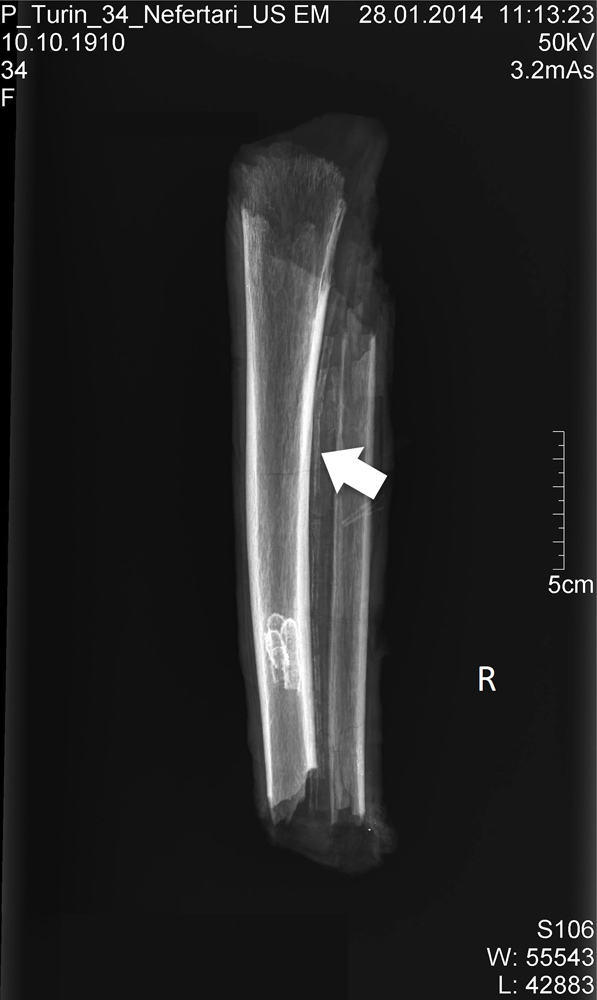

An ancient x-ray

An X-ray of the mummified leg fragments revealed extensive fracturing, most likely postmortem. The legs appear to belong to an adult female who was probably between 40 and 60 when she died, which is consistent with what is known of Nefertari's history, researchers wrote in the journal PLOS ONE. She is last "sighted" in reliefs showing her at a temple opening in the 24th year of Ramesses the Great's reign and is missing in reliefs from a festival in the king's 30th year of rule. That would put her at around 40 to 50 when she died.

On the left, an arrow marks signs of possible arthritis on the bones found in QV 66. On the right, an arrow points to possible calcification in the arteries that runs alongside the tibia. Both arthritis and arterial calcification are signs of age, and possibly indicate minimal physical labor. [Read more about Queen Nefertari's Burial]

An X-ray of the portion of right femur, or thigh bone, ensconced in mummy wrappings. Analysis of the leg bones suggest that they belonged to a middle-age or elderly woman who stood between 5 feet 5 inches and 5 feet 7 inches (165 to 168 centimeters). This interpretation was bolstered by a forensic analysis of the sandals in the tomb, which would have fit someone standing around 5 feet 5 inches.